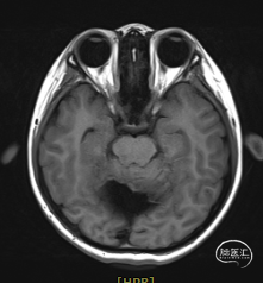

术前MRI

现病史:患者18个月前无明显诱因出现间断头痛,休息后可缓解,开始未予重视,未行特殊治疗。1周前患者无明显诱因出现恶心、呕吐,就诊于当地医院,行颅脑MRI提示:小脑囊实性占位性病变,首先考虑毛细胞星型细胞瘤。现患者为求进一步治疗就诊于我院,门诊以“脑肿瘤”收入院。患者自发病以来神志清,精神可,饮食睡眠正常,二便如常,体重未见明显下降。

小脑肿瘤(毛细胞型星形细胞瘤?)